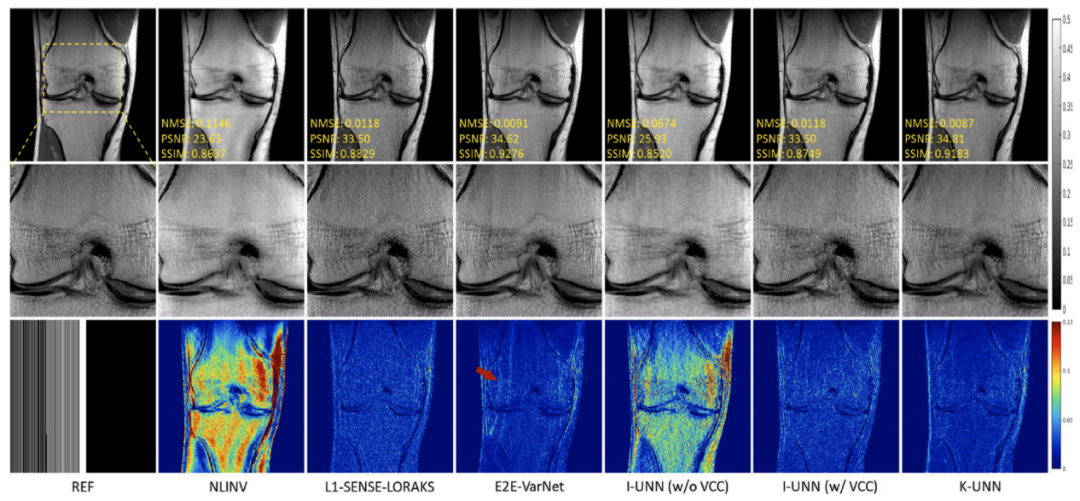

其次,针对现在主流深度学习快速重建方法可靠性不足的问题,提出了零阶算法展开网络的思想,利用网络表示正则化子零阶信息(正则化子本身),增强了网络学习的可解释性,保证了网络算法收敛性和鲁棒(正则)性。实验证明(图2),该方法重建图像质量明显优于传统方法。研究成果发表在医学成像领域著名期刊IEEETransactions on Medical Imaging

图2.测量噪声扰动下,4倍加速重建结果